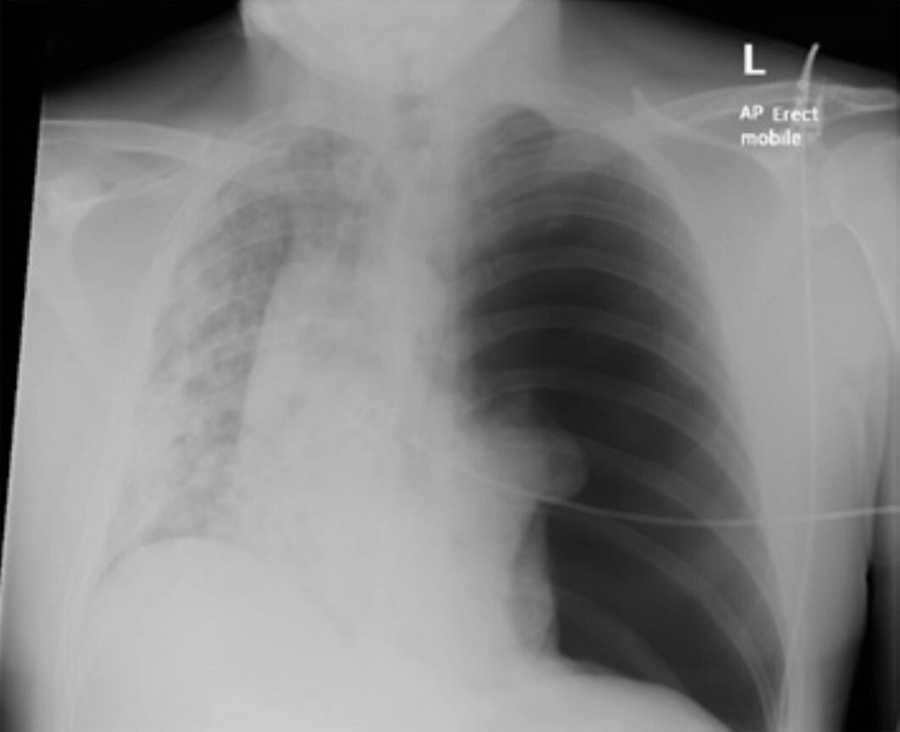

Sau khi chụp X-quang, các bác sĩ phát hiện anh bị xẹp phổi (tràn khí màng phổi).

Hình ảnh chụp lồng ngực giúp phát hiện bệnh nhân bị xẹp phổi

Các bác sĩ cho biết bệnh nhân trở nặng nhanh chóng có thể do nhiễm Covid-19 không được điều trị kịp thời và chuyển sang giai đoạn muộn. Người bệnh khi nhập viện đã bị tràn khí màng phổi áp lực. Điều này dẫn tới đau ngực đột ngột, khó thở, tức ngực, da xanh tím do thiếu oxy, nhịp tim nhanh, mạch yếu, giảm tỉnh táo, giảm ý thức.

Phổi bệnh nhân bị Covid-19 tàn phá với những mảng trắng trên phim chụp